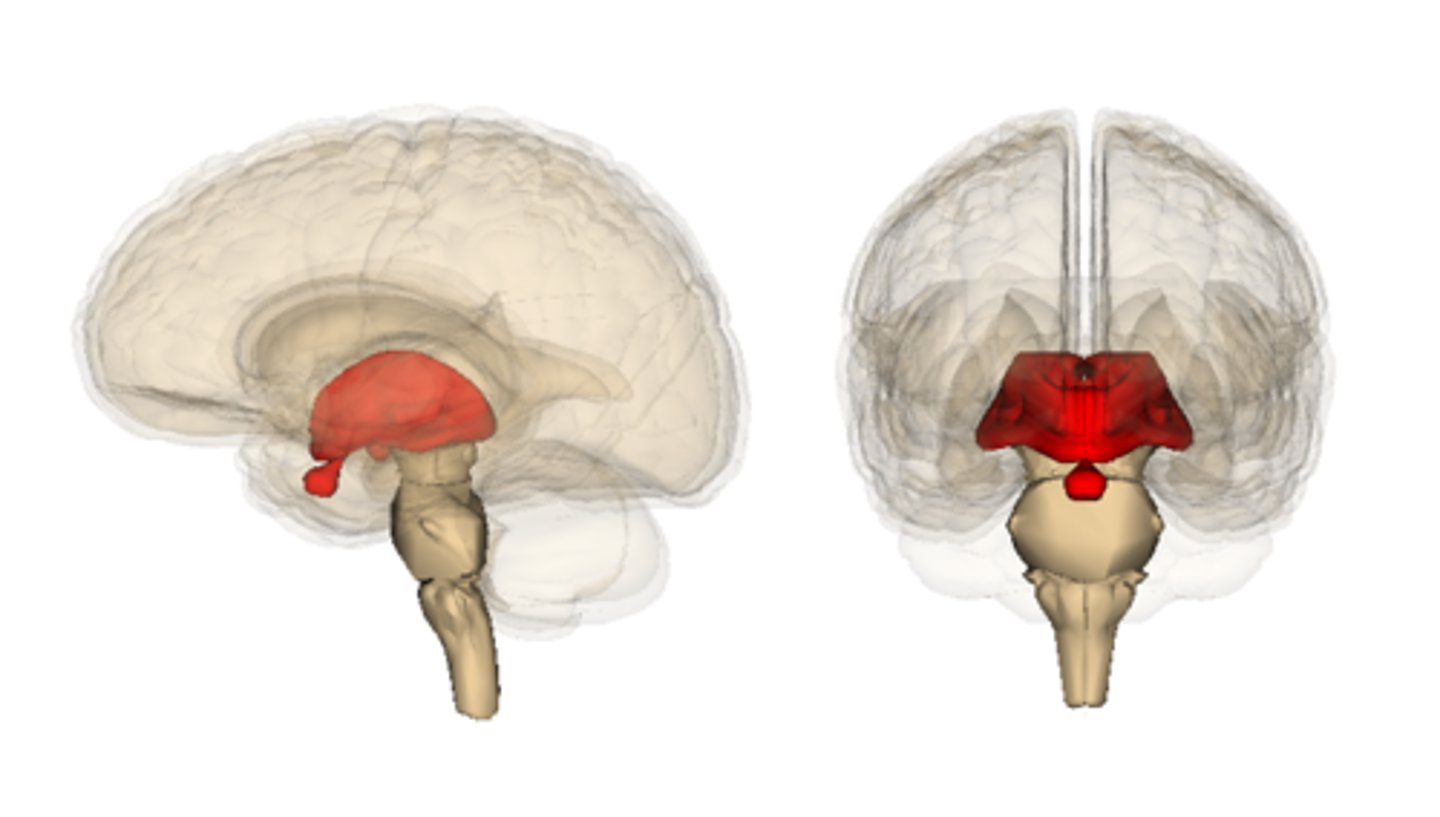

thalamus

hypothalamus

infundibulum

pituitary gland

mammillary bodies

diencephalon